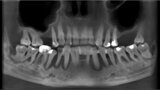

Natychmiastowa implantacja i zaopatrzenie protetyczne pacjentów z zaawansowaną chorobą przyzębia